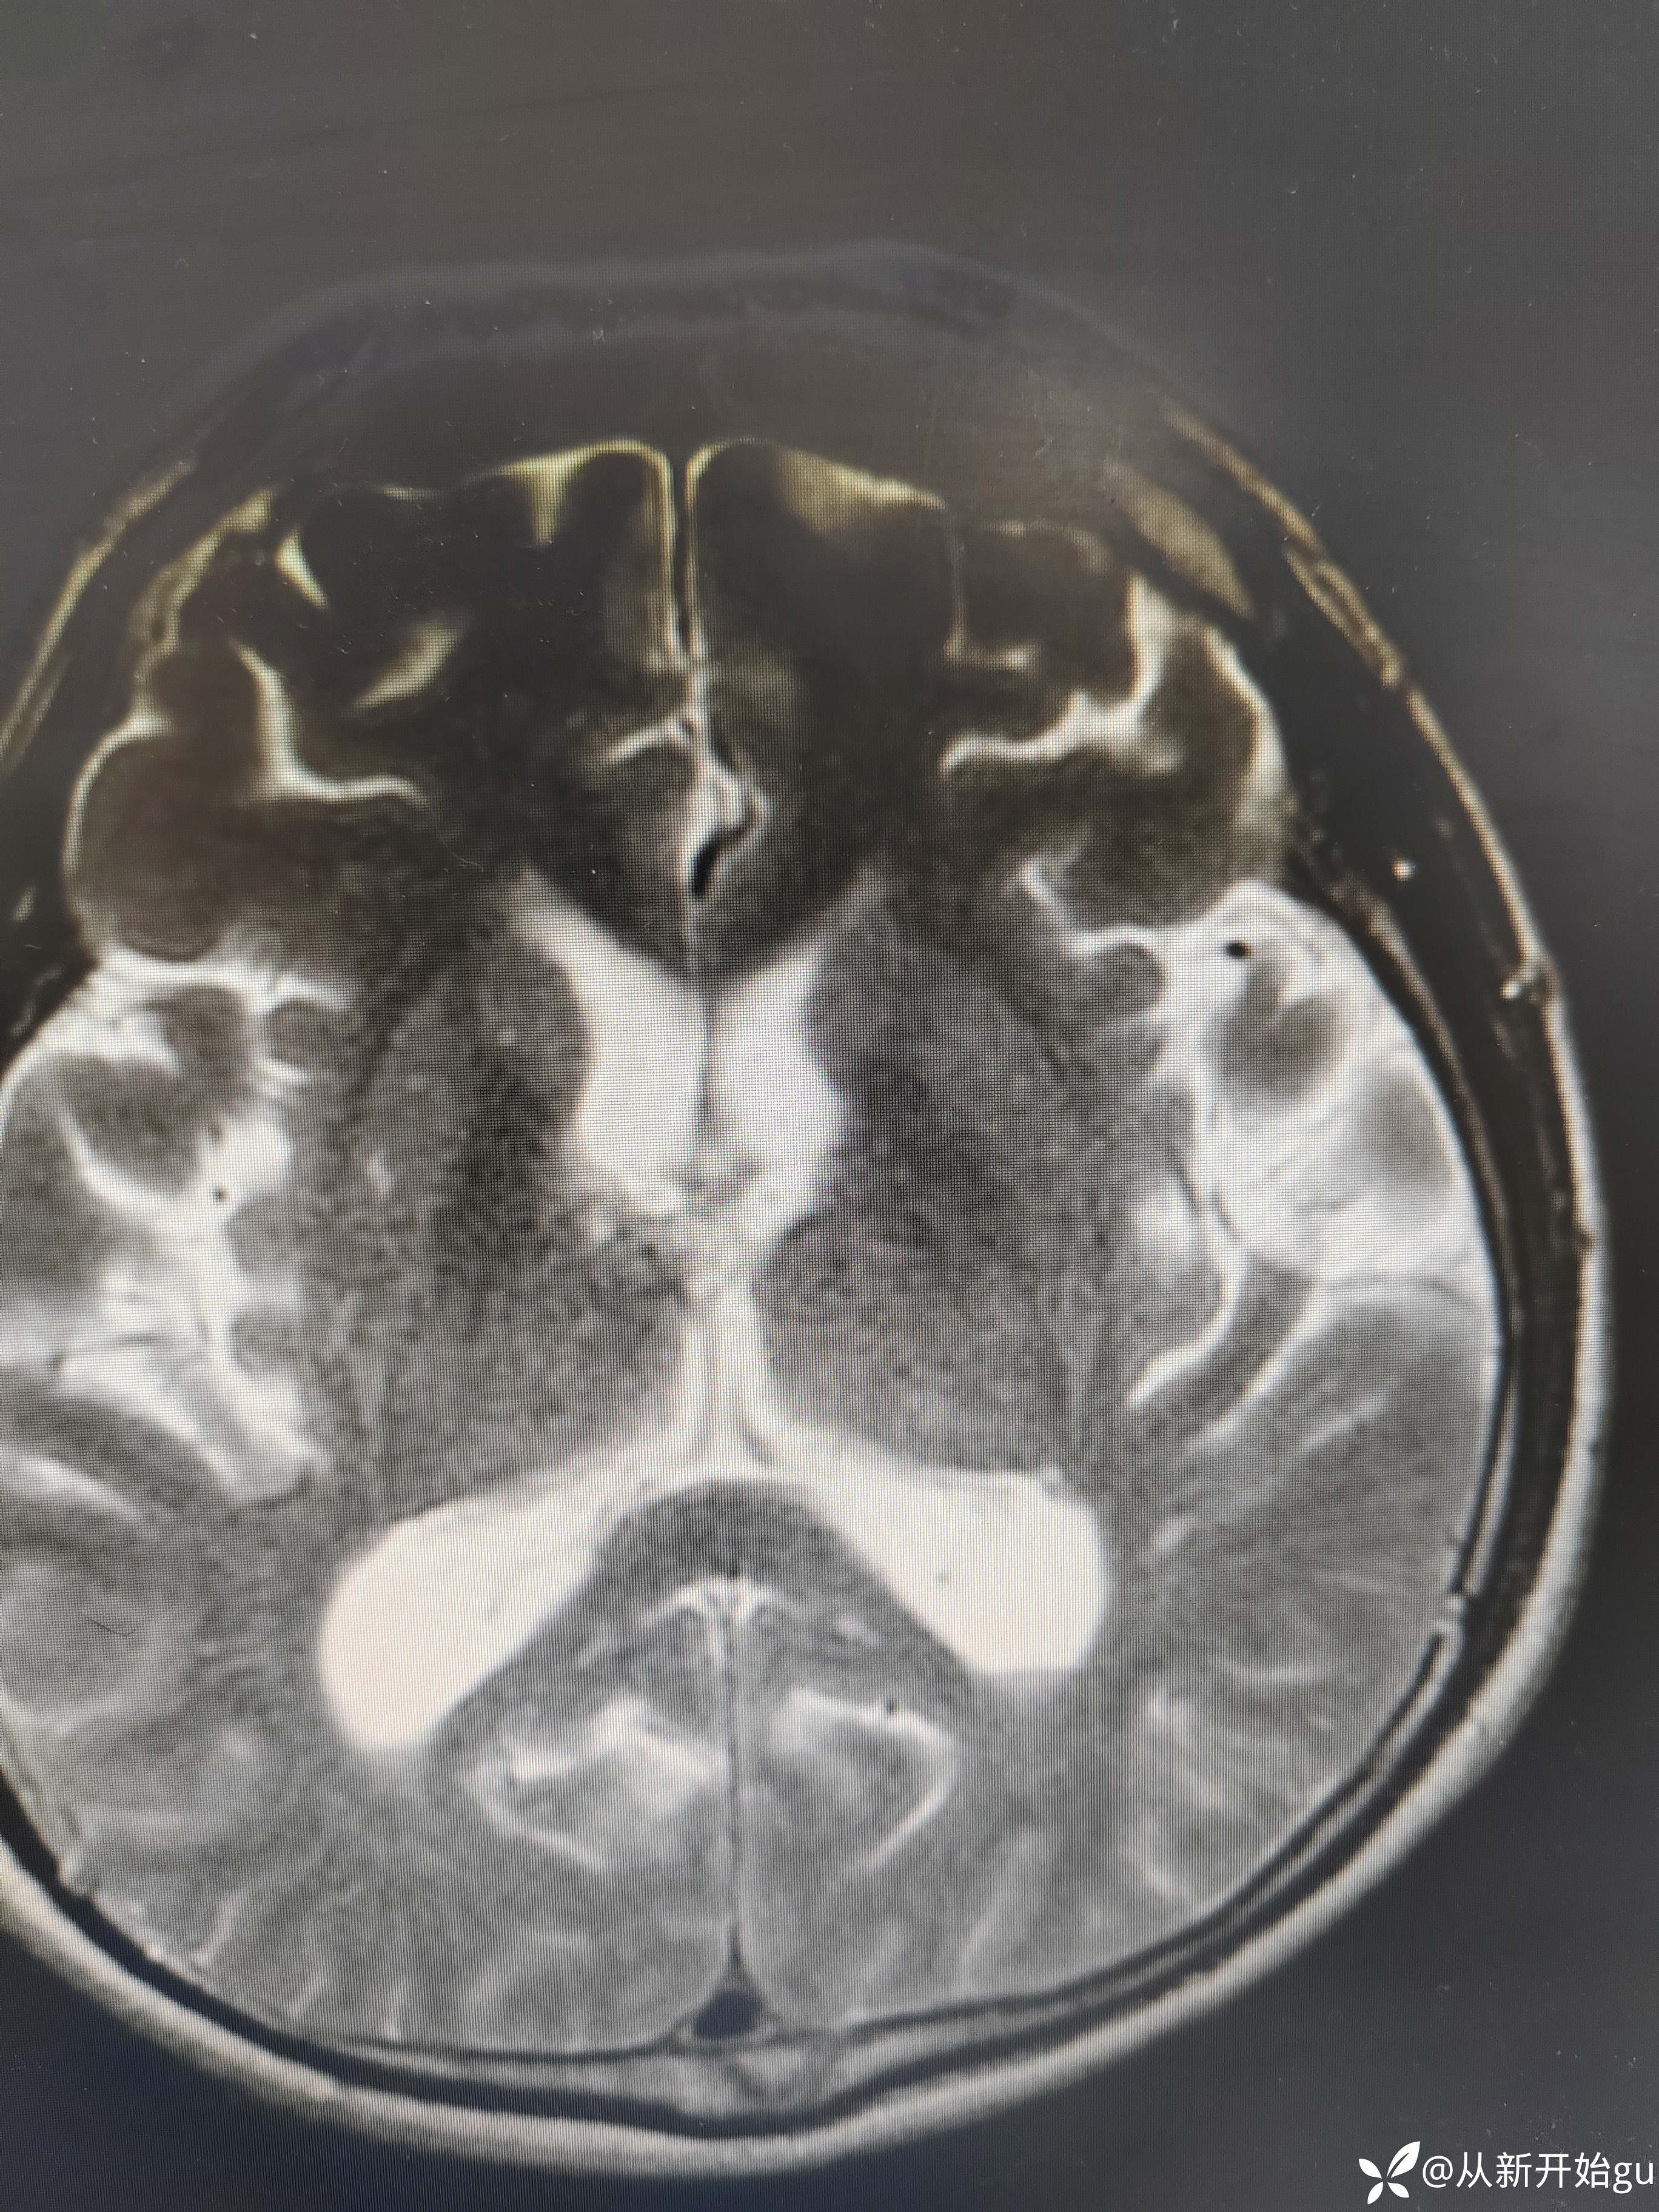

完善核磁:T2

完善核磁:T2